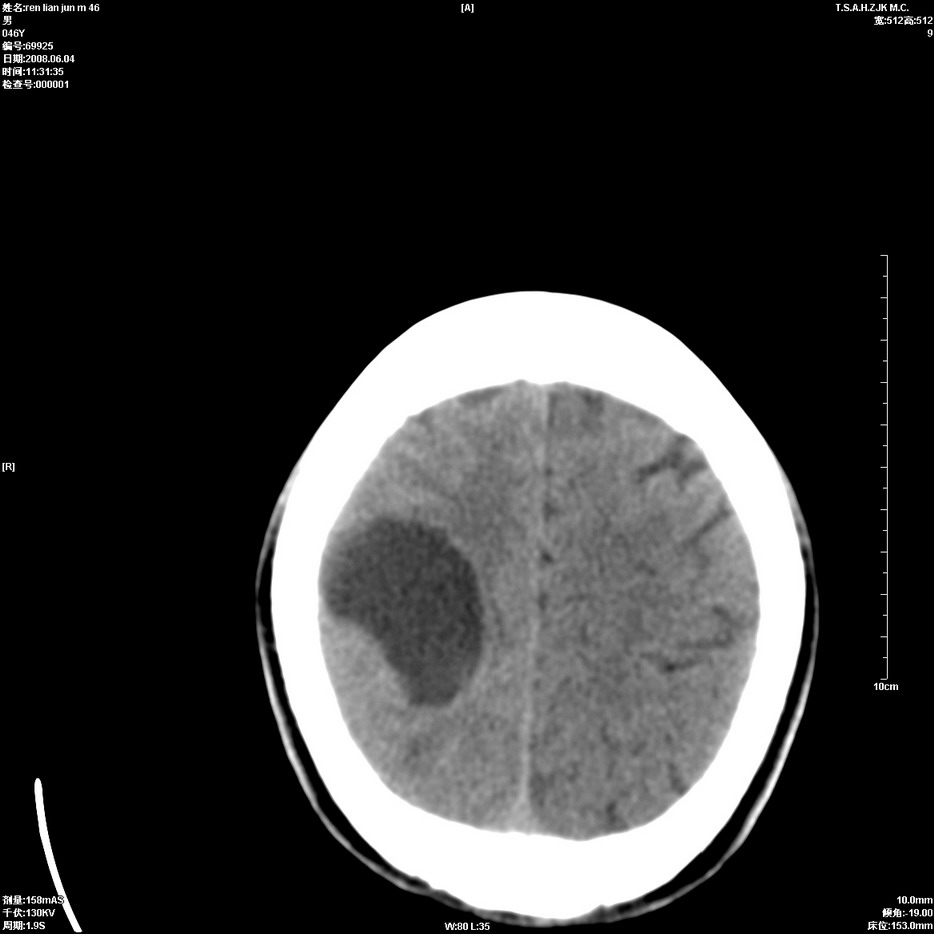

以下是引用qiu999在2008-6-5 17:14:00的发言:[br]考虑右肺中心型肺癌.颅内应做增强检查.

以下是引用形影不离在2008-6-5 19:18:00的发言:[br]右肺中心型肺癌并纵隔及左侧腋窝淋巴结转移,颅内应做增强检查。

以下是引用杀毒软件在2008-6-5 18:33:00的发言:[br]支持考虑右肺中心型肺癌,颅内病变是不是转移,不好说